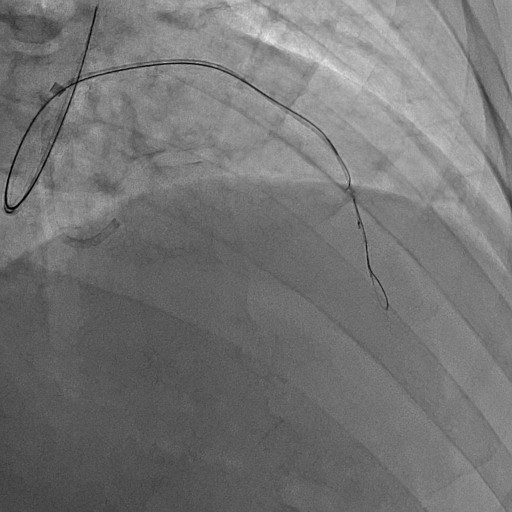

Re-attempted PCI for LAD CTO was planned. The procedure was performed with an 8-Fr, SPB 3.5 SH for the antegrade approach and a 6-Fr IMA for retrograde angiography. Primary antegrade approach was performed because there were no feasible collateral channels. Gaia Next 3 could penetrate the proximal cap of CTO. Since Gaia Next3 could not proceed into the CTO mid portion, the guide wire was escalated to Gaia Next 4. However, Gaia Next 4 advanced into extra plaque space beyond the CTO distal true lumen angiographically. Therefore, we decided to perform tip-detection (TD) method using intravascular ultrasound (IVUS). IVUS revealed that the guide wire proceeded into extra plaque from the CTO proximal portion, although the CTO entry was in the intra plaque space. At first, we tried TD-intra plaque tracking (IPT) in the CTO body. However, Conquest Pro 12 ST (CP-12ST) could not penetrate the CTO body. Therefore, we performed TD-antegrade dissection andreentry (ADR). Eventually, CP12 ST succeeded to puncture the distal true lumen supported by a Caravel. We implanted a drug-eluting stent, which resulted in successful revascularization.